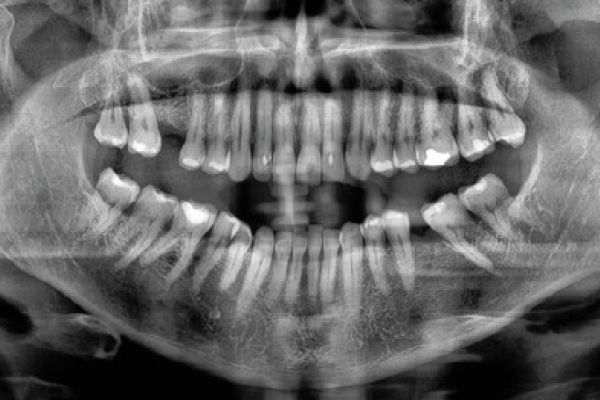

Retención de segundos molares mandibulares: evaluación mediante CBCT y consideraciones terapéuticas ante un caso clínico